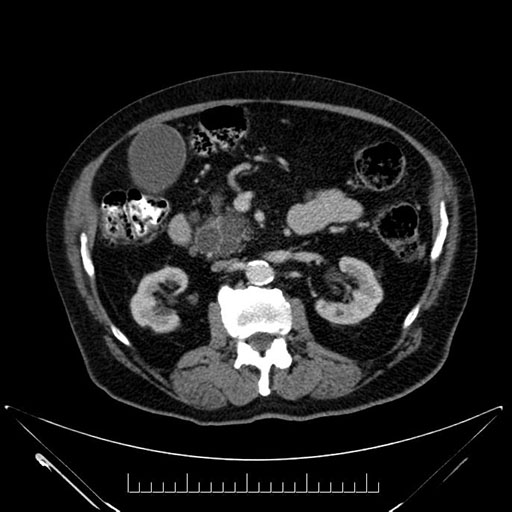

Imaging Analysis

Look through the patient's CT scan to identify any areas of concern for the necessary procedure.

Based on your CT findings, which issue(s) would give reason for "planned slowing down moment(s)" in this case?